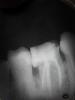

Nadzivany Опубликовано 26 августа, 2013 Автор Поделиться Опубликовано 26 августа, 2013 Извините, что так долго не выкладывал рентген. Я тоже думаю, что это эмалевая капля, т.к она при зондировании такая же твердая как эмаль и белого цвета. Cначала хотел ее сколоть кюретами, но потом подумал, что может и не получиться, только поцарапаю и нужно ли? Потом я сделал ее плоской, т.к. была в виде шарика и изготовил накладку E.max. Ссылка на комментарий

M@estro Опубликовано 29 августа, 2013 Поделиться Опубликовано 29 августа, 2013 Контрастность на снимке мне лично кажется разной у эмали и "эмалевой капли" Ссылка на комментарий